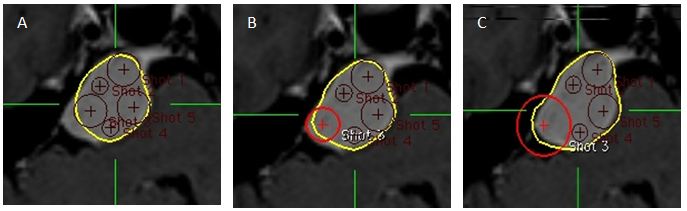

Hình 3: Hình ảnh A, B: đặt shot ở giáp đường biên khối u; C: đặt shot ở xa đường biên khối u

Bệnh nhân Bùi văn U   nam 26 tuổi, chẩn đoán U tuyến tùng, chỉ định xạ phẫu dao gamma quay (RGK) liều 16Gy”

Kỹ thuật 4: Sử dụng các shot trung tâm